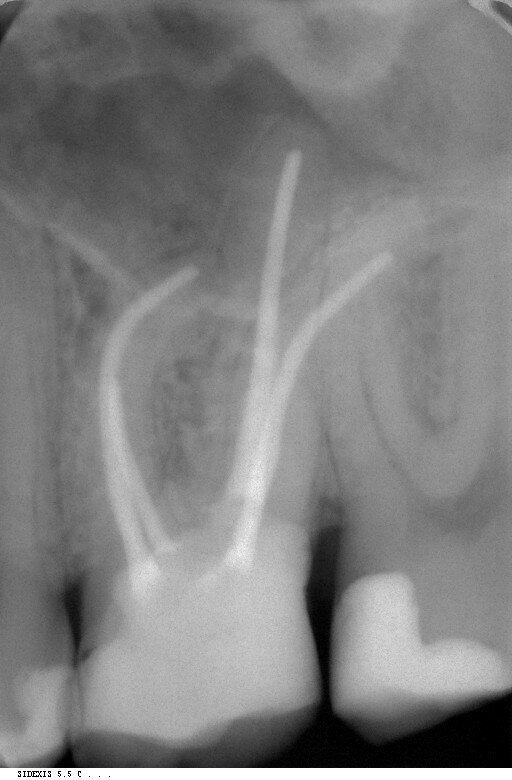

Fig. 2: File surface under the microscope. (Image: COLTENE)

COLTENE’s HyFlex EDM NiTi file system with its modular design and comparatively simple handling was used for the actual preparation of the canal. The sequence more or less functions according to a modular system: depending on the indication and the respective anatomical conditions, the dentist can select from a large number of different file sizes and special files. The HyFlex EDM greatly simplifies the process, especially for beginners in mechanical preparation, owing to its special material properties. The abbreviation “EDM” stands for “electrical discharge machining”, a specifically developed manufacturing process which creates a unique surface structure (Fig. 2). The rough, textured surface increases the cutting performance and makes the instrument particularly fracture-resistant. This makes the NiTi file predestined for dentists who want to achieve reliable results quickly with a reduced sequence.